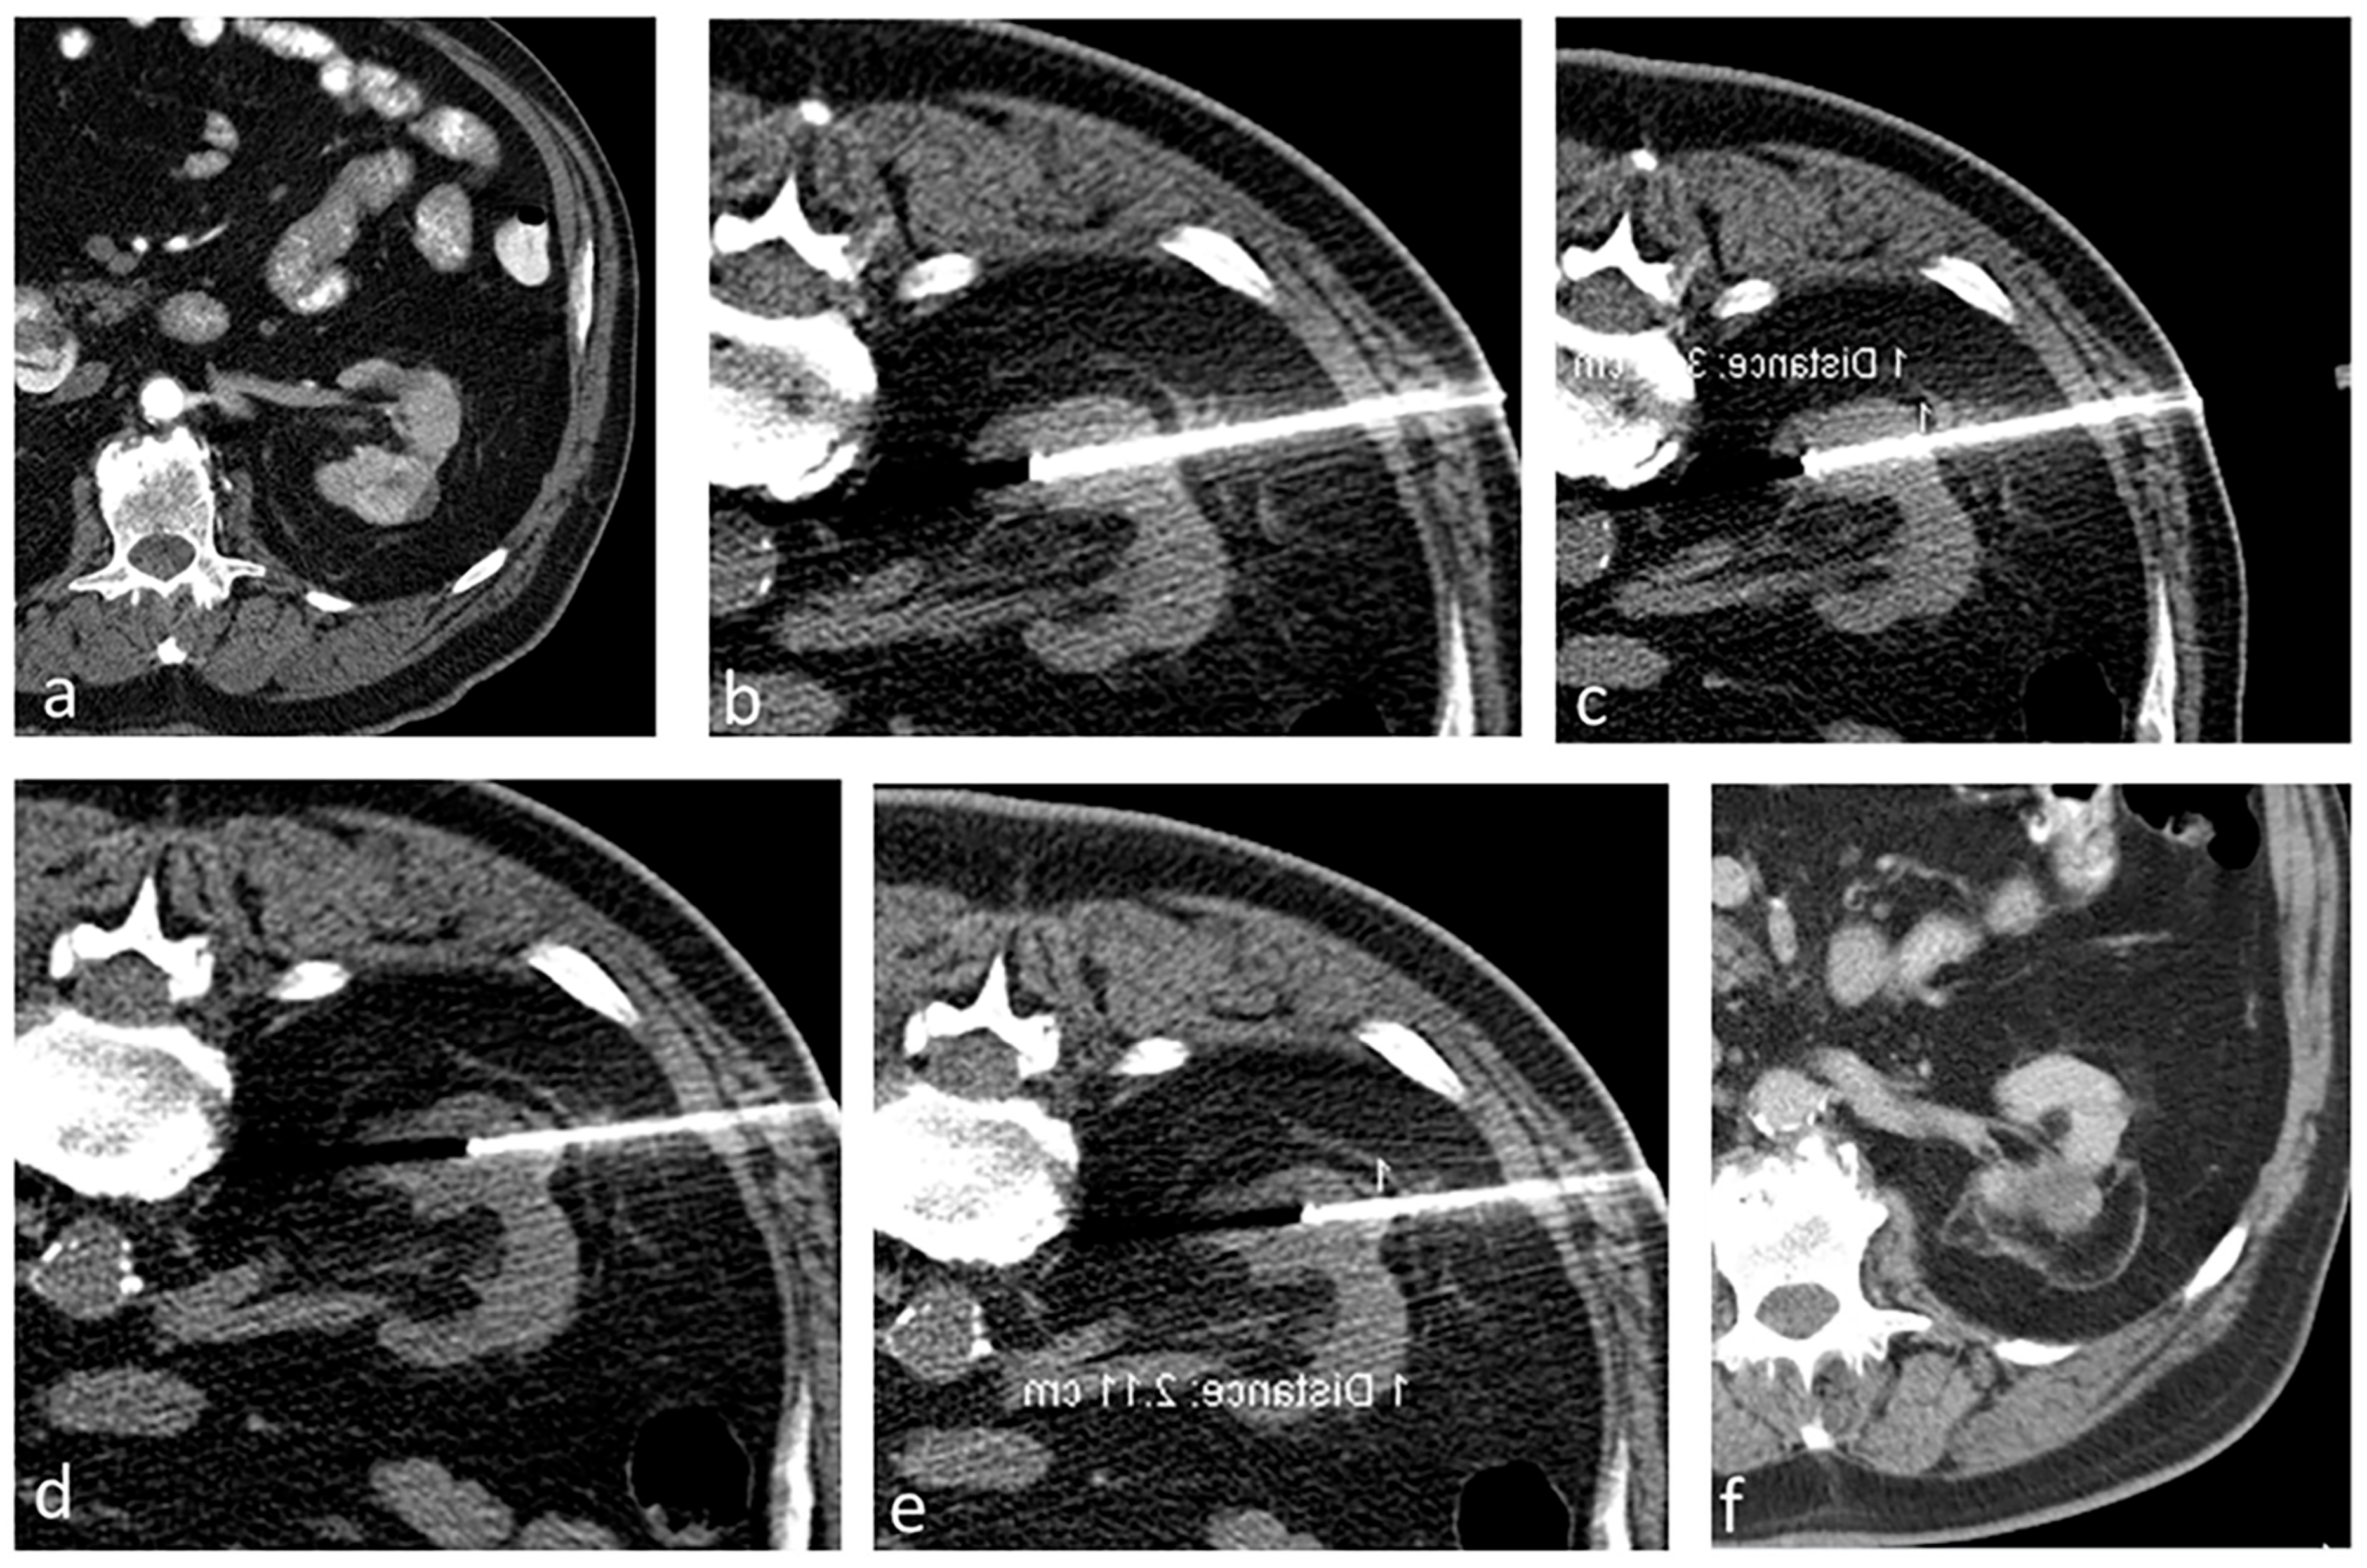

We have detailed our ablation technique in prior publications [7,26]. In summary, we perform the RFA procedures with patients under general anesthesia, guided by computed tomography (CT) imaging (specifically, SOMATOM Definition AS from Siemens Medical Systems, Erlangen, Germany). Once we have planned the ablation, we position the probes and conduct a biopsy (if it has not been carried out beforehand) before initiating the ablation. We use the Cool-tip RF system (Covidien, Mansfield, MA, USA) and employ adjunctive techniques like hydrodissection and pyeloperfusion as necessary. For tumors less than 3 cm, we use 3 cm active tip probes (typically N + 1, where N represents the tumor’s size), positioning them within the tumor. Larger tumors typically require more intricate planning to ensure complete ablation of the tumor. If the craniocaudal size is the dominant dimension (larger than 3), we bisect the tumor at its center and strategize the ablation as though handling two distinct tumors (Figure 1a). Initially, we address the cranial or the caudal part of the tumor using 3 probes, then reposition the 3 probes to target the other part of the tumor (Figure 1b). If the tumor’s width (transverse dimension) is the greater dimension, we again divide the lesion at its center (Figure 1c). First, we position the 3 probes to address the deeper portion of the tumor, and subsequently retract the probes to treat the superficial portion of the tumor (Figure 1d).

Figure 1.

Ablation technique for lesions larger than 3 cm. The craniocaudal size is the dominant dimension (larger than 3); we bisect the tumor at its center (yellow dash line) and strategize the ablation as though handling two distinct tumors (a). Initially, we address the cranial part using 3 probes (black arrows), then reposition the 3 probes to target the more inferior part (b). If the tumor’s width (transverse dimension) is the greater dimension, we again divide the lesion at its center (yellow dash line) (c). First, we position the 3 probes (arrow heads) to address the deeper portion of the tumor and subsequently retract the probes (black arrows) to treat the superficial portion of the tumor (d).